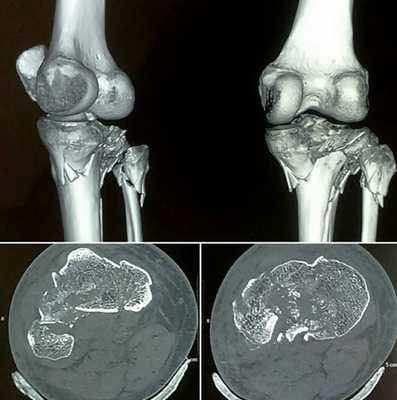

КТ при нестабильности плеча

А - дисплазия гленоида;

В - повреждение Хилл-Сакса (субхондральный перелом), дефект головки плечевой кости после вывиха плеча;

С - повреждение Банкарта (отрыв ободка от костной впадины с вывихом плеча вперед, разрушение краев лопаточной впадины - места прикрепления хряща);

D - повреждение Хилл - Сакса в переднем отделе суставной губы;

Е - 3D-реконструкция переднего вывиха плеча;

F- задний перелом с вывихом плеча.

Наиболее часто КТ плечевого сустава выполняют по поводу травматических повреждений. Они различаются по механизму альтерации: падение на вытянутую руку, прямой удар и пр. Врач-рентгенолог после анализа томограмм выявляет причину, а ортопед определяет оптимальную тактику ведения. Иногда повреждение может быть настолько серьезным, что пациенту необходимо эндопротезирование плечевого сустава.

Рентгенограмма и компьютерная томограмма у пациента с тяжелым переломом и вывихом правого плечевого сустава до операции